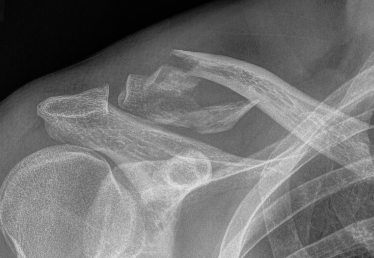

Nonunion

Robinson and Cairns JBJS Am 2004

- cohort of 100 displaced Type II fractures treated nonoperatively

- 11 had symptomatic nonunion

- 21 had asymptomatic nonunion

- reasonable outcome scores with nonunion

- recommended non operative treatment in middle aged / elderly

Non-Union

Options

1. Large fragment - bone graft / ORIF

2. Small fragment - excise open / arthroscopic

ORIF of nonunion with large distal fragment

Open excision of small distal nonunion fragment